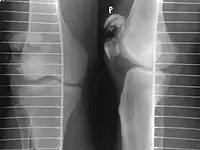

Tension band wiring: front and side view

Most patella fractures are transverse or comminuted, hence the quadriceps mechanism is disrupted and they are treated by a combination of wires in a tension band construct. This unites the fractured bones, reconstructing the straightening mechanism of the leg.[5][6]